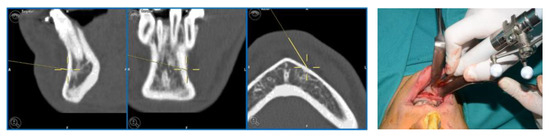

In light of the suspicion of an ameloblastoma recurrence, surgical removal was recommended, opting for the use of tracked instruments with surgical navigation. A maxillary bite was created, followed by the attachment of 5 screws with varying spatial orientations that would function as fiducial markers. This bite was employed to maintain the mandible in a consistent position both during the preoperative CT scan acquisition and throughout the entire surgical procedure (Figure 13).

Figure 13.

Intraoperative placement of the same bite used for acquiring mandibular CT scan images. The bite ensures the mandible remains in the same position as during the virtual surgical planning.

During the surgical procedure, the Dynamic Reference Frame (DRF) was positioned in the right parietal bone, and the positions of the screws on the bite were recorded as fiducial markers. The same bite used during the CT image acquisition was utilised for this purpose. The navigation accuracy was less than 0.5 mm. The piezoelectric was registered by attaching a tracking tool with three reflective spheres to the handpiece, and the tip of the piezoelectric was marked and utilised as a reference point for navigation. The navigation accuracy was found to be less than 1 mm.

Under the guidance of the tracked piezoelectric device, the resection of the lesion was carried out as per the preoperative plan, with macroscopically preserved healthy bone margins, including the lower and posterior mandibular border (Figure 14).